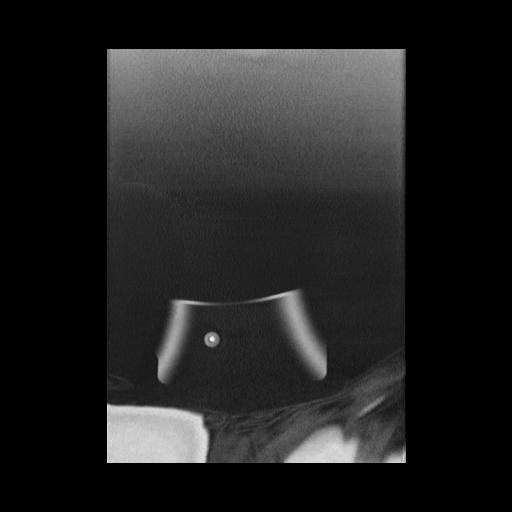

16 HUESO,,Coronal,2.000,HUESO,Coronal,